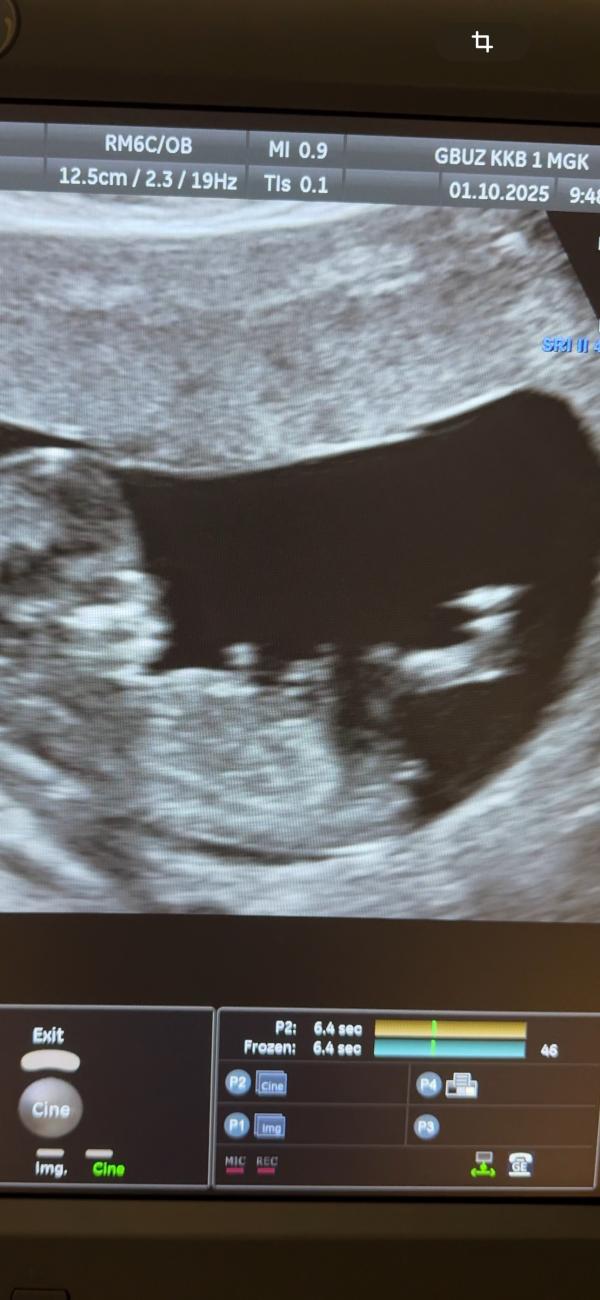

Девочки,погадайте)))

Вообще на девочку похожа,две полоски. Как половые губки ☺️У нас так же было.

И мне показалось что это яйца😂Мой узист предположил мальчика,а сегодня генетик предположил девочку🫠😂